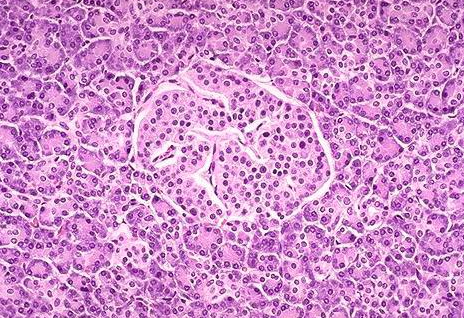

ТОКИО, 2024 оны дөрөвдүгээр сарын 10 /Yomiuri/. Японы Олон улсын анагаах ухааны үндэсний төвийн мэргэжилтнүүдээр ахлуулсан эрдэмтдийн баг нойр булчирхайн даавар үүсгэдэг дотоод шүүрлийн эсийг (Лангерхансын эс) гахайнаас хүнд шилжүүлэн суулгах мэс заслыг ирэх онд хийхээр төлөвлөж байна.

Цусан дахь сахрын хэмжээг бууруулах үүрэгтэй энэ эсийг 1-р хэлбэрийн чихрийн шижинтэй өвчтөнд шилжүүлэн суулгах юм. Ингэснээр өвчтөнийг инсулиний тарилгаас хамааралт байдлыг ихээхэн багасгана гэж эрдэмтэд найдаж байна. Өвчтөний биемахбодь хүлээж авахаас татгалзахгүй байлгахын тулд цусан дахь сахрын хэмжээ ихсэх үед инсулин ялгаран гарах жижиг нүхт бүхий 0.5-1 мм-ийн голчтой тусгай капсулд шилжүүлэн суулгасан эсүүдийг хийх аж.